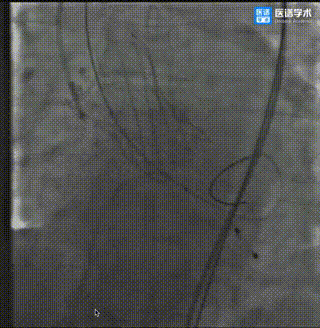

术前冠脉造影(右冠开口狭窄并伴有夹层)

右冠行PCI手术治疗

主动脉根部造影

导丝轻松跨瓣

20mm球囊预扩

20mm球囊预扩,无明显腰征,少许瓣周漏(靠近二尖瓣方向),未见冠脉阻挡,选择使用TaurusElite®️AV26瓣膜。

TaurusElite®️轻松过弓

瓣膜定位

TaurusElite®️缓慢展开

瓣膜工作状态

检查位置及效果

瓣膜释放

瓣膜释放后形态位置良好

造影少量返流

(靠近二尖瓣方向)

选择22mm球囊后扩治疗